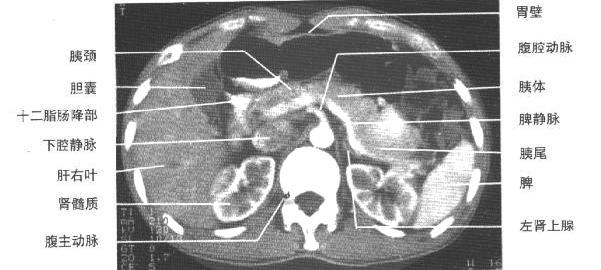

| 胰体、腹腔动脉、脾静脉层面(增强)